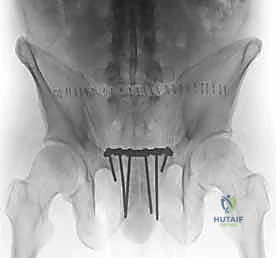

بمجرد استعادة الوضع الصحيح للعظام، يقوم الدكتور هطيف بتثبيتها باستخدام صفيحة معدنية متخصصة (غالباً صفيحة إعادة بناء متعددة الثقوب مصنوعة من التيتانيوم أو الفولاذ المقاوم للصدأ الطبي). يتم تثبيت هذه الصفيحة عبر المفصل العاني باستخدام مسامير قشرية (Cortical Screws) تُغرس بعمق في عظام العانة الصلبة لضمان تثبيت قوي يتحمل ضغط الجسم.

بعد التأكد من قوة التثبيت من خلال الأشعة السينية داخل غرفة العمليات (Fluoroscopy)، يتم إغلاق الجرح على طبقات باستخدام خيوط جراحية تجميلية قابلة للامتصاص، مع وضع أنبوب تصريف (درنقة) لمنع تجمع السوائل.